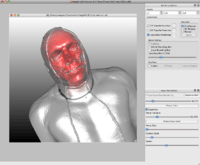

A screenshot of ImageVis3D, demonstrating the ClearView [1] feature on the visible human male dataset. | |

- supports 1D and 2D transfer functions as well as isosurface extraction and the ClearView rendering technique